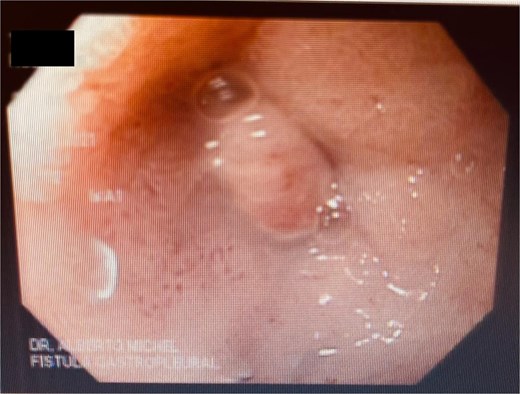

A 41-year-old female with a history of arterial hypertension underwent vertical sleeve gastrectomy for super obesity (BMI 52). She developed a complication of leakage in the cardia region, resulting in a gastropleural fistula and significant bacterial colonization, necessitating a left lobectomy. Persistent cough led to her referral to our department, where endoscopy revealed a 15-mm fistulous orifice. Previous endoscopic management with pigtails and endoscopic glue had failed, prompting initiation of EVAC therapy. Changes were made every 3–5 days, showing partial improvement. A treatment variant was applied by placing the sponge without suction (Fig. 4), promoting granulation tissue formation and enabling the patient to continue oral intake without lung leakage risk.

A cavity with an EVAC sponge is seen during endoscopic treatment.

This variant, leaving the sponge without a nasogastric tube and negative suction, aimed to manage the fistula while stimulating tissue granulation. Currently, although the fistula persists, she is tolerating oral intake with symptom improvement, and granulation tissue is present, suggesting that the fistula is in the process of closing (Fig. 5).

After sponge replacements, granulation tissue is observed in the area where the fistula was located.